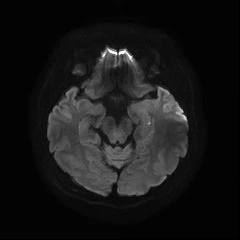

diffusion MRI, : 급성 뇌손상(뇌졸중) 확인에 민감

Diffusion MRI (급성기 뇌손상 확인을 위한 MRI),

이렇게 여러 종류의 MRI 촬영을 했네요!

영상을 보면.. 위에서, 옆에서, 밑에서.. 여러 각도에서 입체적으로 찍었어요.

급성기 뇌송상은 일반 MRI에는 나타나지 않고,

Diffusion MRI에만 보이는 거라..

그것을 먼저 촬영하고..

Diffusion MRI (Diffusion-Weighted MRI, DWI) : 확상강조영상을 의미하며, 주로 급성 뇌손상 특히 뇌경색(뇌졸중) 확인에 사용됨. 일반 MRI와 달리 분자의 움직임(diffusion)을 영상화. 급성 뇌경색이 생기면 물 분자의 이동이 제한되므로 조기 발견 가능. 증상이 나타난 직후에도 뇌경색을 민감하게 확인할 수 있음. 뇌경색처럼 갑자기 생긴 작은 손상을 빨리 확인할 수 있는 특수 MRI.